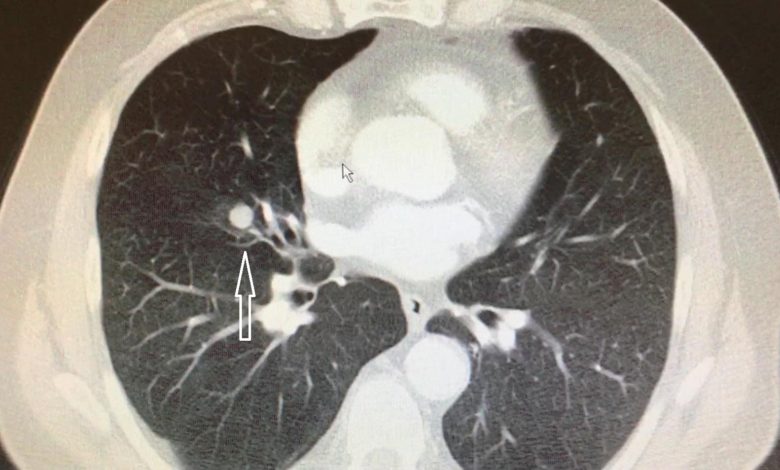

Nodülün kıvamına tomografi ile karar veriyoruz. Tomografi bize radyasyon ışınları ile insan vücudunu istediğimiz kalınlıkta ve yönde dilimleyebilmemizi sağlıyor. 1 mm’den 10 mm’ye kadar. Böylece nodülü üç boyutlu olarak analiz edebiliyor, boyutunu, hacmini ve şeklini ortaya koyabiliyoruz. Bazı nodüller zatürreyi andırıyor. Bazıları ise denizkestanesini, küçük bir lastik topu veya yer elmasını andırabiliyor. Bu şekillerin hepsi bize nodülün kanser olup olmadığı konusunda fikir veriyor. 3 cm’den küçük dokulara nodül diyoruz, ama 1 cm sınırı bizim için önemli. Niye mi? Çünkü akciğer kanserini 1 cm’den küçük yakaladığımızda hastalarımızın neredeyse tamamını (%90’ın üzerinde başarı şansı var) iyileştirebiliyoruz. Bu oran 2 cm’de %80’e, 3 cm’de %70’e düşüyor. Boyut arttıkça akciğer kanserinden kurtulma ihtimalimiz tedricen azalıyor. %10 önemlidir, hele terazinin bir tarafında insan hayatı olunca daha da önemli hale geliyor.

Sigara içiyorsanız ve 55 yaşın üzerinde iseniz, akciğerinizde sert kıvamlı, kenarları düzensiz, 15 mmden büyük nodül görüldüyse, bunun kanser olma şansı %50. Sigara miktarı ve yaş arttıkça bu ihtimal daha da artıyor. Oysa sigara içmeyen ve 40 yaş altındaki kişilerde böyle bir nodülün kanser olma ihtimali %10’dan daha az… Yani sigara ve yaş karar verirken dikkate aldığımız en önemli iki kriter. Diğer önemli kriterler ailede akciğer kanseri hikâyesi, amfizem varlığı, cinsiyet, nodülün sertlik derecesi ve nodülün büyüklüğü. Hatta nodüllerin kanser riskini hesaplayan internet ve cep telefonu programları var. Makalenin başında yazdığımıza geri dönelim. Tesadüfen çekilen bir göğüs tomografisinde, 45 yaşında sigara içen bir erkekte 6 mm’lik bir nodül tespit edilirse ne yapacağız?

Çünkü böyle bir nodülün kanser olma ihtimali sadece %0.4. Yani binde 4. Yapılacak en iyi şey belirli aralıklarla 1-2 kez takip etmek ve sigarayı bırakmak! Hekimlere yardımcı olmak amacıyla birçok rehberler yayınlanıyor. Bu uluslararası rehberlerde 6 mm’nin altındaki nodüllere bir girişim önerilmiyor. Yani boşu boşuna ameliyat olmuyorsunuz! Nodül 1 cm’in üzerinde ise kanser ihtimali arttığı için ya radyolojik/cerrahi biyopsi, ya da yakın takip gerekiyor. En ufak bir şüphede ameliyat ile çıkarmak hayat kurtarıcı oluyor. Akciğerler, vücuttaki tüm kanın içinden geçtiği narin organlar. Kanser geliştiğinde, bu yaygın damar ağı hastalığın hızla yayılmasına neden oluyor. Daha küçükken hastalığı kontrol etmek önemli! Akciğerdeki çok küçük nodüllerde tedirgin olmayın, ama tedbiri de elden bırakmayın. En büyük hediye olan hayatınızı riske atmayın.